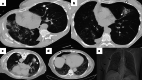

Image-guided percutaneous lung ablation has proven to be a valid treatment alternative in patients with early-stage non-small cell lung carcinoma or oligometastatic lung disease. Available ablative modalities include radiofrequency ablation, microwave ablation, and cryoablation. Currently, there are no sufficiently representative studies to determine significant differences between the results of these techniques. However, a common feature among them is their excellent tolerance with very few complications. For optimal treatment, radiologists must carefully select the patients to be treated, perform a refined ablative technique, and have a detailed knowledge of the radiological features following lung ablation. Although no randomized studies comparing image-guided percutaneous lung ablation with surgery or stereotactic radiation therapy are available, the current literature demonstrates equivalent survival rates. This review will discuss image-guided percutaneous lung ablation features, including available modalities, approved indications, possible complications, published results, and future applications.